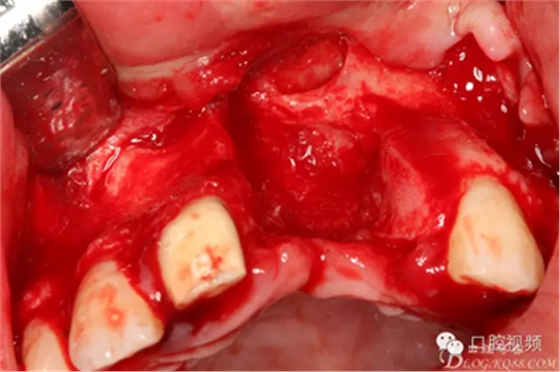

圖6.拆除前牙烤瓷橋后,21區(qū)域死骨清晰可見,22牙根暴露2/3,觸目驚心!

圖8.切開、翻瓣、完整暴露壞死部分牙槽骨

圖9.牙槽骨壞死達(dá)鼻底